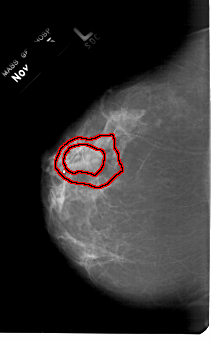

A_1169_1.LEFT_MLO

LEFT_MLO LINES 6871 PIXELS_PER_LINE 4366 BITS_PER_PIXEL 12 RESOLUTION 43.5 OVERLAY

FILE: A_1169_1.LEFT_MLO.OVERLAY

TOTAL_ABNORMALITIES 1

ABNORMALITY 1

LESION_TYPE MASS SHAPE IRREGULAR MARGINS SPICULATED

ASSESSMENT 5

SUBTLETY 2

PATHOLOGY MALIGNANT

TOTAL_OUTLINES 2

BOUNDARY

CORE